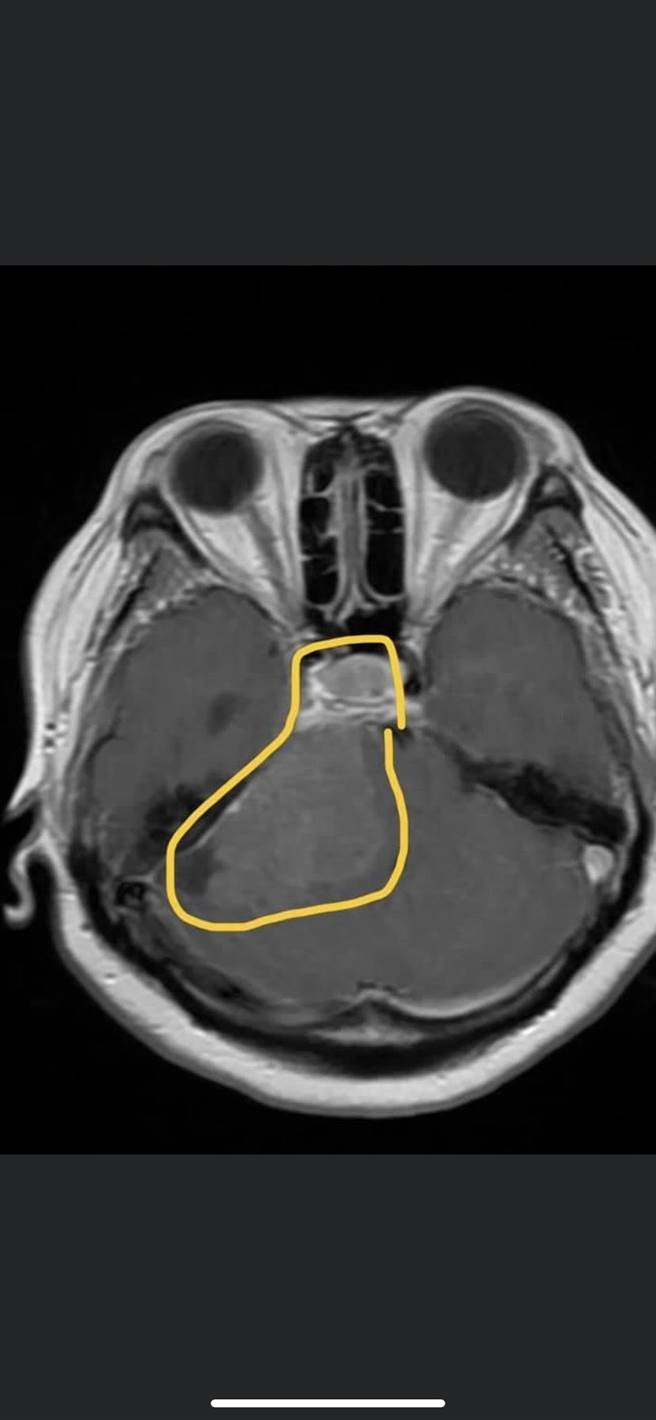

李漢忠說,陳姓患者除有「水腦症」,另腦部深處有7公分大「小腦橋腦角腫瘤」合併腦幹壓迫,和3公分大的「蝶鞍上腫瘤」壓迫視神經,而「水腦症」正是腫瘤因腫塊效應導致腦室阻塞,相當罕見,患者2個月內開3次腦部手術,幸好腫瘤順利切除,只要定期回醫院追蹤即可。

李漢忠指出,透過術中移動式電腦斷層3D導航系統,降低病患受傷機率,在2個月內進行了3次手術,順利的將病灶切除,幸好證實是良性的腦膜瘤。術後陳小姐對症狀改善很有感受,表示「大小便比較順,走路也不會一直往後倒。